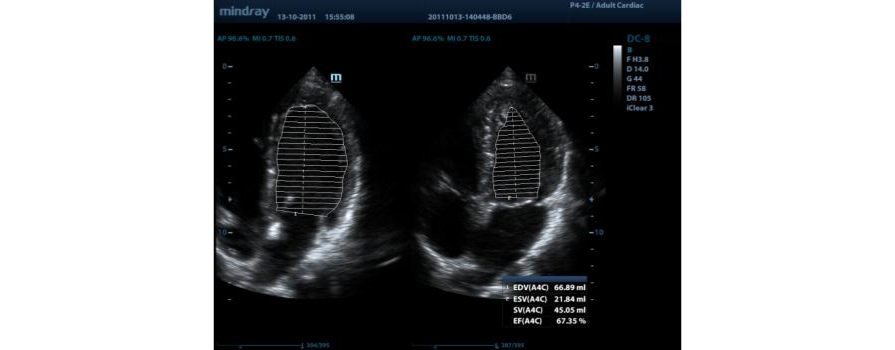

AutoEF

Cara pintar menganalisis klip gema 2D untuk mengenali bingkai diastol/sistol dan output EDV/ESV/EF secara otomatis, dsb. yang dihasilkan oleh metode Simpson.

LV Otomatis

Prosedur pengukuran sederhana untuk ventrikel kiri yang ditingkatkan dengan fungsi pelacakan otomatis dan koreksi manual yang mudah.